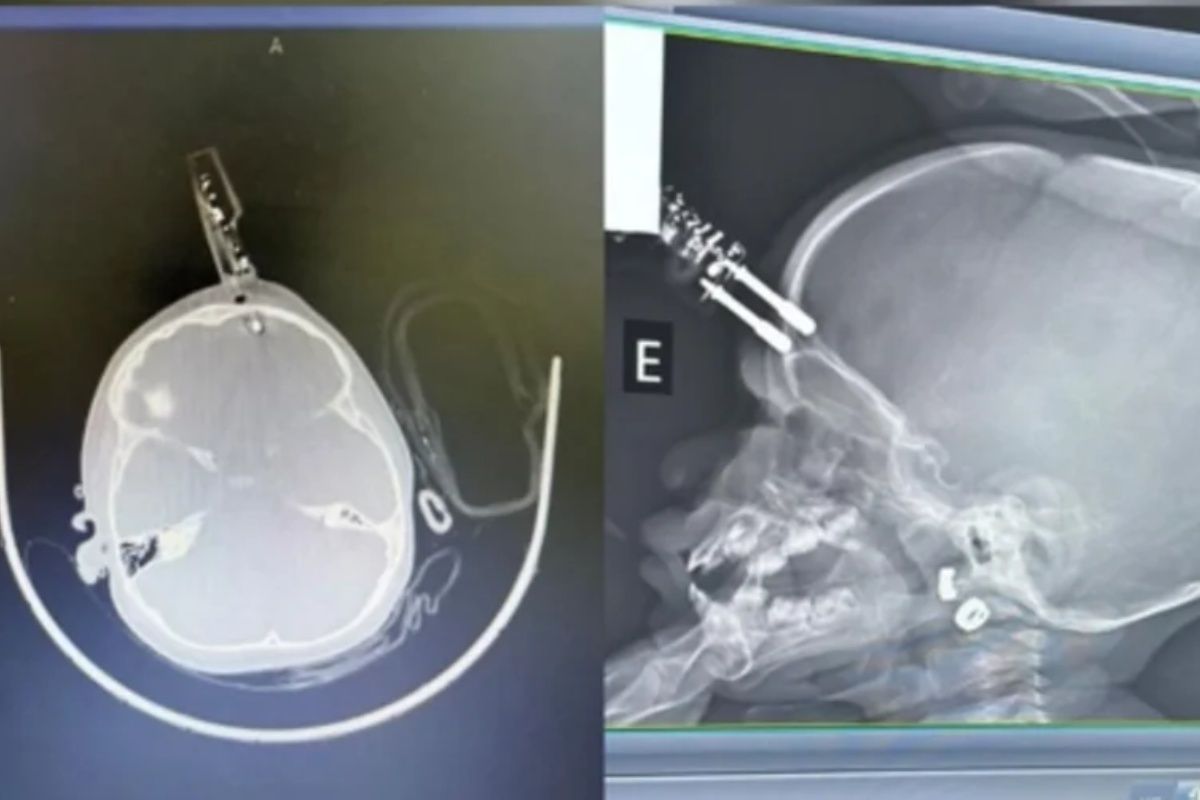

Ela acionou o Samu, que realizou o atendimento e encaminhou as duas para a UPA. Segundo o neurologista Bruno Castro, que atendeu o caso, o carregador chegou a perfurar o crânio da menina, provocando uma fratura.

Ela foi inicialmente atendida na Unidade de Pronto Atendimento (UPA) de Divinópolis e, em seguida, transferida para o Hospital São João de Deus, onde passou por cirurgia imediata para retirada do objeto, correção da lesão e contenção de um pequeno sangramento.

Após o procedimento, a criança foi levada ao Centro de Terapia Intensiva (CTI), onde permaneceu por 36 horas. Ela passou por tomografia de controle e apresentou boa evolução clínica.

Por se tratar de um objeto considerado contaminado, a menina permaneceu internada para receber antibióticos, mas, segundo o médico, está se recuperando bem e deve ter alta em breve.

“Ela está super bem e é mais provável que se recupere sem déficit”, afirmou o neurologista. Castro explicou ainda que, embora qualquer lesão cerebral possa gerar risco de convulsões ou epilepsia no futuro, a probabilidade de sequelas é baixa, desde que haja companhamento médico.